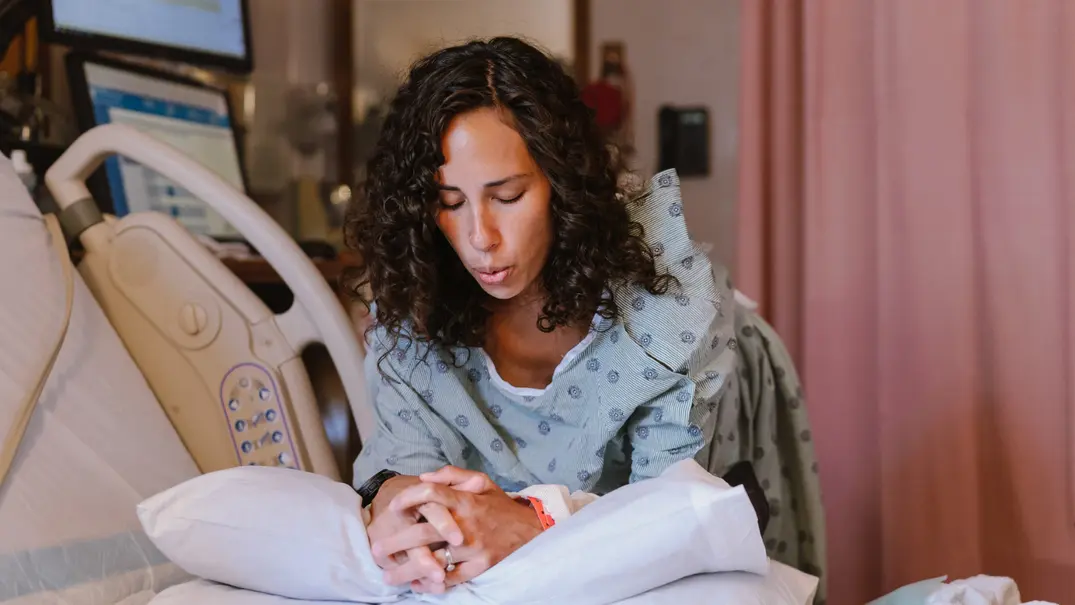

Spontane Geburt oder doch ein Kaiserschnitt? Jede Frau, die zum ersten Mal schwanger ist, beschäftigt sich in den Monaten vor der Geburt mit dem Ablauf und hat viele Fragen. Wie wird die Geburt meines Kindes ablaufen? Kann ich spontan gebären oder wird es ein Kaiserschnitt? Bekomme ich mein Kind im Krankenhaus oder wähle ich ein Geburtshaus oder bring ich meine Kind vielleicht Zuhause zur Welt? Wie kann ich mich am besten auf die Geburt vorbereiten und wie kann mein Partner mich unterstützen? Und welche Mythen rund um das Thema Geburt stimmen eigentlich wirklich?